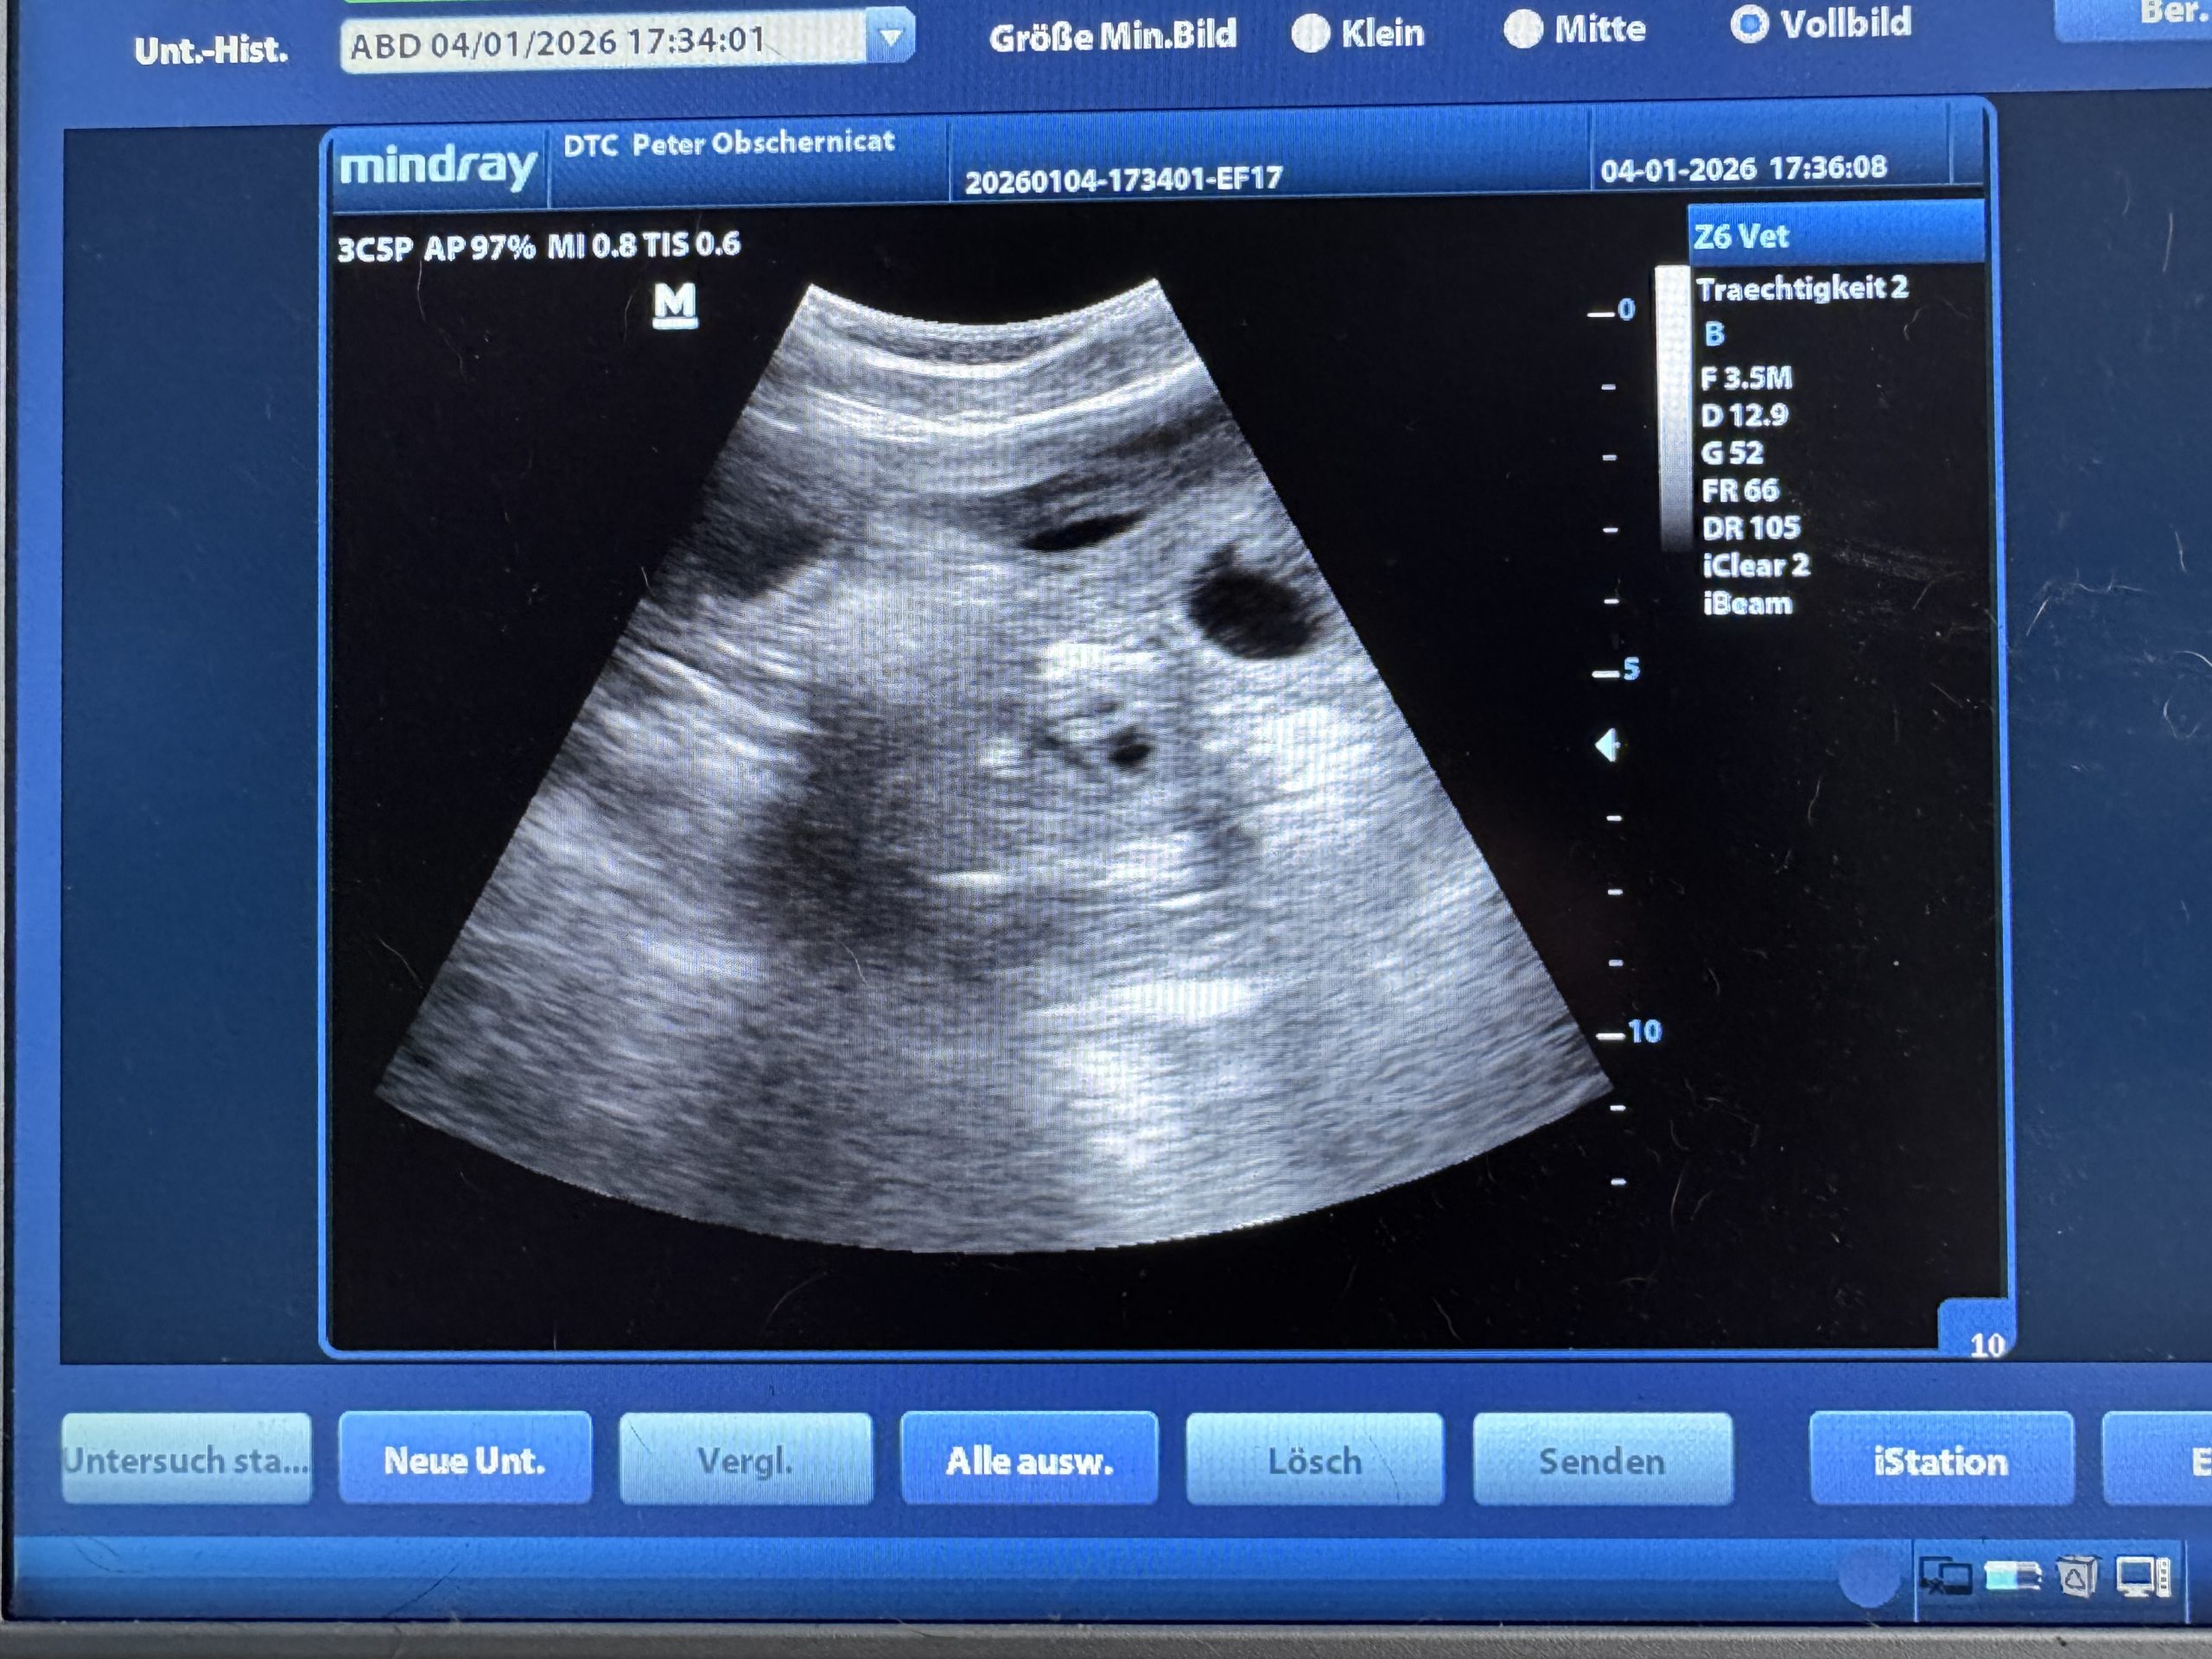

K-Wurf is coming